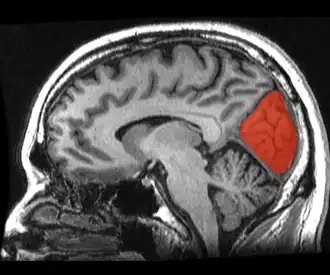

Sagittal MRI slice with the cuneus and lingual gyrus shown in red. | |

The cuneus (from Latin 'wedge'; pl.: cunei) is a smaller lobe in the occipital lobe of the brain. The cuneus is bounded anteriorly by the parieto-occipital sulcus and inferiorly by the calcarine sulcus.